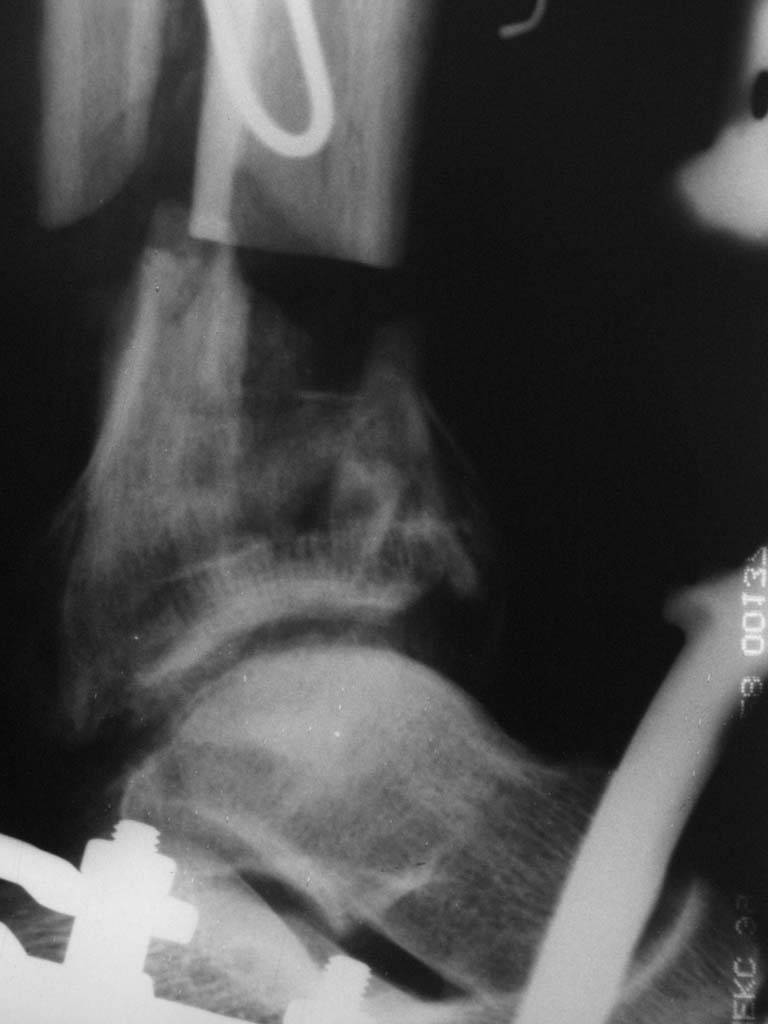

|  |  |  |  status localis на 14.11.08 (В ране визуализируется сухожилие.) | Больной А, 40 лет, находится в клинике с 15.10.08 с диагнозом: Сочетанная травма. Ушиб головного мозга лёгкой степени тяжести. Компрессионные переломы тел 12 грудного и 5 поясничного позвонков без неврологических осложнений. Закрытый внутрисуставной многооскольчатый перелом дистальных метаэпифизов обеих костей правой голени со смещением. Открытый внутрисуставной многооскольчатый перелом дистальных метаэпифизов обеих костей левой голени со смещением (см. Р-граммы). Хронический алкоголизм. Доставлен СМП после падения с 5-го этажа (не суицид). При поступлении состояние тяжелое. Глубокое оглушение. Дыхание самостоятельное, адекватное. Гемодинамика стабильная. По внутренней поверхности левой голени, в нижней трети, рвано-ушибленная рана 10-6 см, из раны выстоит проксимальный отломок большеберцовой кости, рана обильно загрязнена землёй. Интенсивная терапия в условиях реанимационного отделения, вытяжение за правую пяточную кость, параартериальная блокада обеих нижних конечностей, гипсовая лонгета на левую нижнюю конечность, ас-повязка на рану. Через 4 часа после поступления оперирован: после неоднократного промывания раны тёплой проточной водой с мылом, антисептиками, при ревизии определяется земля в канале проксимального отломка на глубину 3 см..., отсутствие надкостницы на концах дистального и проксимального отломков на 3 см. Удалено значительное количество мелких костных фрагментов, перемешанных с землёй, выполнена ПХО раны, резекция проксимального конца большеберцовой кости на 3,5 см, ЧКДО аппаратом Илизарова. Рана не ушивалась. В последующем перевязки раны с "Левомеколь", через 3 недели с момента травмы в ране определялись грануляции, нежизнеспособный конец дистального отломка. 10.11.08 ВХО раны, резекция дистального отломка на 3 см, перемонтаж аппарата наружной фиксации (см. Р-граммы). Отломки сближены на 2 см (остеотомию малоберцовой не делали). В настоящее время (5 сутки после операции) незначительное количество серозного отделяемого из раны, имеется дефект кости 4 см (см. Р-граммы). В последующем склоняемся к перемонтажу аппарата наружной фиксации, остеотомии малоберцовой кости в области повреждения, сближении отломков. По заживлению раны удлинение левой голени на 4 см. Однако, некоторыми высказывалось мнение о необходимости артродеза. Представляем рентгенограммы левой голени при поступлении, после повторного оперативного лечения и фото st.localis на 14.11.08. Будем очень благодарны за критику, комментарии, пожелания и мнения о дальнейшей тактике лечения.

В случае гладкого заживления раны, при условии положительного решения вопроса с металлом, планируем перемонтаж аппарата Илизарова, дополнительную резекцию дистального отломка, выведение полокости голеностопного сустава в правильное положение (см. боковую Р-грамму), одномоментно остеотомия большеберцовой кости. После восстановления длинны голени, по всей видимости, артродез голеностопного сустава.